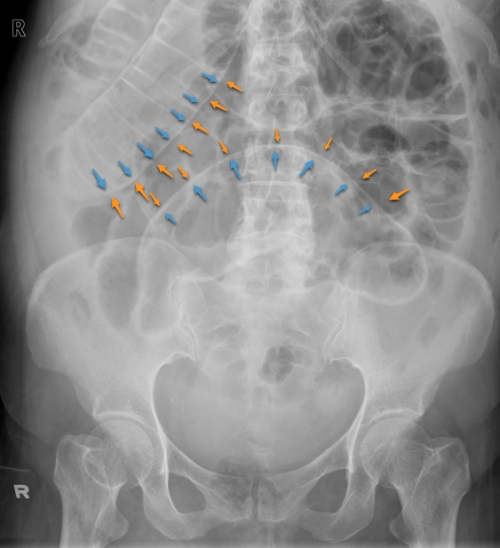

What does this AXR show?

It shows small bowel obstruction (valvulae conniventes) as well as a perforation (Rigler’s sign - you can see the bowel wall on both sides of the lumen).